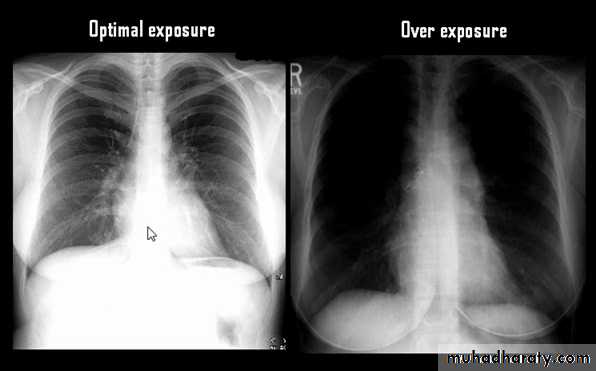

Techniques - Projection

P-A (relation of x-ray beam to patient)

Supine view (AP)

Lateral view .

lateral decubitus .

(in which the pt put on the suspected side & X-ray is taken (such as in pleural effusion).

LORDOTIC VEIW

Thoracic inlet view : to see hilar shadows, cardiophrenic angle shadow & right middle lobe collapse.

Routine Examination includes

P-A view , Other supplementary views are done according to the case. So all Patients admitted to hospital should have P-A X-ray In standing erect view in complete inspiration